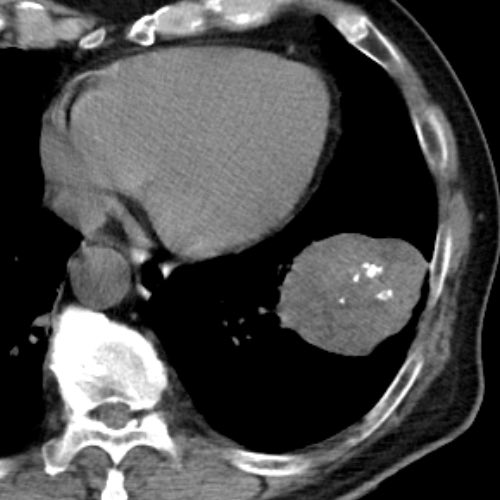

大きくなってからは、CT値が-30HUを下回る低吸収域を示す部分が

まだら状に混在し、ポップコーン様の粗大な石灰化も明瞭に認められ

診断は容易となっています。かなり増大したという点が手術をした理由です。

以上です。今日は、8年の間に増大し、6cm程度の巨大腫瘍となってしまった

肺過誤腫の症例を提示させていただきました。